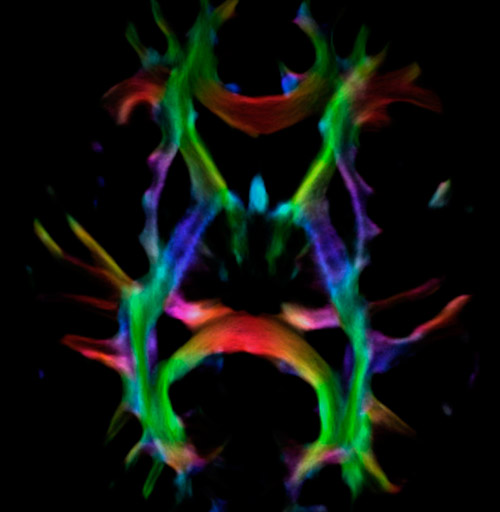

Fiber tractography of the corticospinal tract with seed region of the posterior limb of the internal capsule. Different processing based on the same data.

All images were created from the same acquisition in a child using Ingenia 3.0T CX and 32-channel dS Head coil. Diffusion data was acquired at b-values 0, 500, 1000, 2000, 3000. The use of high b-values (3000 s/mm2) effectively suppresses extra-axonal water signal and provides high angular resolution.

Fiber tracking from the left and right hippocampi to the fornix.

Fiber tracking from the left and right hippocampi to the fornix (green), and the corticospinal track based on a seed region of the posterior limb of the internal capsule.